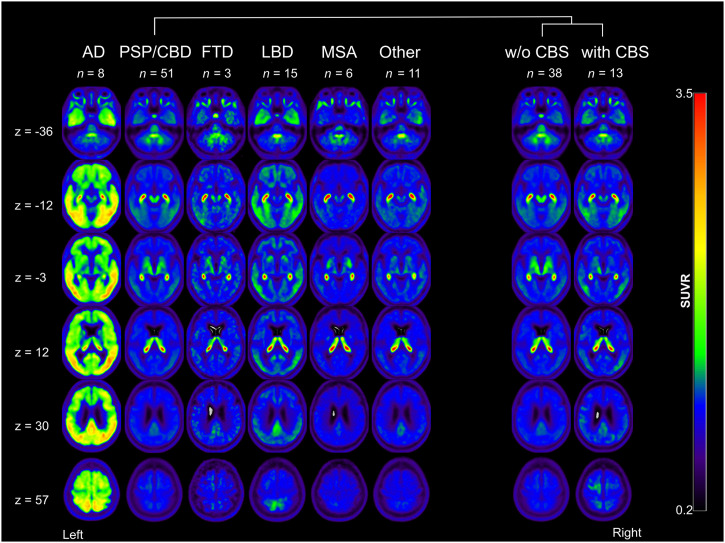

Visual Ratings of [18F]Florzolotau PET Binding

Figure 2 depicts representative transaxial slices of average [18F]florzolotau PET images of each group. Figure 3 and Supplemental Table 1 illustrate the proportion of visual ratings for 4R-like or AD-like patterns in the different patient groups. The 3 raters reached substantial agreement for the classification of 4R-like (κ range, 0.78–0.97) and AD-like (κ range, 0.88–0.96) patterns (higher agreement between more experienced raters, 0.97 vs. 0.84).

The expected 4R-like pattern from the literature was replicated by the present sample (Fig. 2). This 4R-like pattern was more highly prevalent (84.3%) and expressed (mean score, 2.0 ± 1.1) in the PSP/CBD group than in all other disease groups (pooled prevalence, 11.6%; mean score, 0.26 ± 0.75; P < 0.0001 compared with the 4R group). The pattern was observed in most PSP/CBD cases with moderate to strong expression (12/51 [23.5%] and 24/51 [47.1%], respectively), whereas only few patients with PSP/CBD showed no or mild pattern expression (8/51 [15.7%] and 7/51 [13.7%], respectively). Consensus ratings did not significantly differ between patients without CBS (2.2 ± 1.1) and with CBS (1.5 ± 1.2, P = 0.08). However, the gradient of binding was significantly different: patients with PSP/CBD without CBS (PSP, according to consensus diagnoses) showed more pronounced subcortical binding (gradient rating, 0.3 ± 0.7), whereas those with CBS exhibited more cortical binding (gradient rating, 1.6 ± 0.5; P < 0.0001).

In turn, the 4R-like pattern was not detected in any AD and LBD cases. One of 3 (33.3%) FTD cases was rated to show a strong 4R-like pattern (not present in the remaining 2 cases), whereas only 1 of 6 (16.7%) MSA cases showed moderate 4R-like pattern expression (not present in the remaining 5 cases). Three of 11 patients with other diagnoses were rated as showing a mild, moderate, and strong 4R-like pattern (final diagnoses of nonneurodegenerative disease, subcortical leukoencephalopathy, and nonneurodegenerative disease, respectively).

The AD-like pattern was also well replicated in the present sample (Fig. 2). Consensus ratings indicated strong and mild AD-like pattern expression in 6 of 8 (75.0%) and 2 of 8 (25.0%) patients, respectively (i.e., prevalence of 100% and mean score of 2.5 ± 0.9 in the AD group). The AD-like pattern was also frequently present in other patient groups (pooled prevalence, 67.4%), albeit at a lower magnitude (mean score, 1.2 ± 1.1; P < 0.01 compared with the AD group): moderate and strong AD-like pattern expression was rated in a substantial fraction of LBD cases (moderate, 4/15 [26.7%], 3/7 PD and 1/4 PDD; strong, 6/15 [40.0%], 2/4 PDD and 4/4 DLB) and a few PSP/CBD cases (moderate, 7/51 [13.7%]; strong, 5/51 [9.8%]; at higher frequency in patients with CBS [6/13] than without CBS [6/38]). The remaining LBD (5/15 [33.3%], 4 PD and 1 PDD), PSP/CBD (39/51 [76.5%]), FTD (3/3), and MSA (except 1/6 with moderate pattern expression) patients showed no or mild AD-like pattern expression (Fig. 3). In patients with other diagnoses, AD-like pattern ratings were roughly equally distributed across the 4 grades (Fig. 3).

The present study was conducted in a real-world sample of patients with parkinsonism that reflects the expected indication for tau PET in the clinical routine. It demonstrates that a visually rated 4R-like binding pattern on [18F]florzolotau PET allows the identification of patients with PSP/CBD with high sensitivity and specificity. In addition, a gradient of the 4R-like pattern toward cortical binding was highly associated with the presence of CBS in patients with a 4R-like pattern. Although the AD-like pattern of [18F]florzolotau binding as a marker of (early) AD copathology or possibly primary age-related tauopathy was common in this representative clinical cohort, it did not significantly affect the diagnostic performance of the 4R-like pattern.

Visual evaluation of the 4R-like pattern revealed ROC AUC of 0.87 for the discrimination of PSP/CBD from all other groups, which remained largely unchanged when focusing on proper parkinsonian syndromes (0.91) or excluding all AD patients (0.86). This aligns well with previous findings, which showed AUC between 0.87 and 0.94 for a volume-of-interest–based approach to separate PSP from α-synucleinopathies with [18F]florzolotau PET (ref. 1), and it suggests that the high specificity in this representative sample (88%) is not driven by easy identification of AD-related syndromes. This study validates promising earlier data in a larger clinical cohort that includes not only or predominantly patients with probable or later-stage PSP or PSP-RS and somewhat artificial controls (e.g., AD or healthy controls). Instead, the present sample appropriately covers the entire spectrum of syndromes and diagnoses that would be expected in parkinsonism with possible 4R tauopathies based on clinicopathologic studies (as explained in the introduction). Moreover, current estimates for sensitivity (84%) and specificity (88%) of the 4R-like pattern on [18F]florzolotau PET suggest an advantage in comparison to the second-generation ligand [18F]PI-2620, which allows detection of PSP-RS with high sensitivity (85%, at 77% specificity), whereas non–Richardson-type PSP (65%) and Aβ-negative CBS (65%) were detected with noticeably lower sensitivity (ref. 2,ref. 4). The mean disease duration of patients with PSP enrolled in the aforementioned studies (ref. 1,ref. 2) was longer (4.1 and 3.8 y) than that of the current PSP/CBD group (3.2 y), highlighting the possible value of [18F]florzolotau for earlier diagnosis. Moreover, the simple acquisition protocol and the easy-to-implement workflow for visual image analysis provide practical advantages compared with [18F]PI-2620 (60-min acquisition and kinetic modeling) (ref. 2). Cases of FTD and MSA with 4R-like pattern expression (1 patient each) are in line with the previous literature and may be related to the occurrence of 4R tau pathology in nonfluent variant primary progressive aphasia and behavioral variant FTD (ref. 26,ref. 27) or to misclassification because of possible off-target binding of [18F]florzolotau in MSA (ref. 28).

Previously described binding patterns for clinically likely 4R tauopathies and AD were well replicated in the present cohort (ref. 1,ref. 3,ref. 8). This also applies to the binding gradient of the 4R-like pattern. Most patients correctly assigned to the PSP/CBD group had no CBS. These patients showed subcortical dominant binding in 81.8%. However, all cases with CBS (clinical consensus diagnosis of PSP-CBS and CBD-CBS with an 4R-like pattern score ≥ 1, 5 cases each) showed predominantly cortical binding (60.0%) or balanced binding between cortical and subcortical structures (40.0%). This was also the case in 6 patients with PSP/CBD without clinical CBS (balanced, 1 PSP-RS; cortical predominance, 3 PSP without a clear predominance type and 2 PSP with predominant frontal presentation). Although a comparably severe 4R tau pathology in cortical areas can be expected in PSP with predominant frontal presentation (ref. 9), this may imply that cortical 4R tau pathology precedes the clinical manifestation of cortical symptoms and CBS in the other cases. Therefore, a possibly predictive value of the binding gradient requires further research. Overall, the results confirm the approach of the current study to consider the binding of [18F]florzolotau not only as a diagnostic marker for a subset such as PSP-RS but also as a marker for the entire group of 4R tauopathies.

Although the 4R-like pattern showed high specificity for PSP/CBD and was not observed in AD and LBD cases, patients exhibited an AD-like pattern of varying degrees across all diagnostic groups. Besides in AD and in line with a previous study (ref. 29), strong AD-like pattern expression was predominantly observed in patients with PDD and DLB. Although Aβ status was not systematically evaluated in this study, this finding suggests the actual presence of AD-type copathology, which frequently occurs besides α-synuclein pathology in PDD and DLB (ref. 30). Given the substantial prevalence of mild AD-like pattern expression across all groups, it is tempting to speculate that this may be caused by primary age-related tauopathy (ref. 31). However, because of the unknown amyloid status of most patients (n = 72), early AD copathology in elderly subjects as the origin of this pattern expression may be possible. Overall, our additional analyses (i.e., logistic regression analysis of combined AD and 4R patterns and exclusion of AD patients) imply that the frequent occurrence of the AD-like pattern has no relevant effect on diagnostic accuracy in the present clinical context.